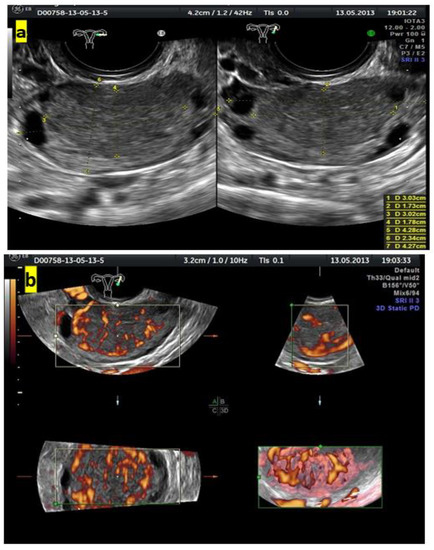

- Koneczny, J.; Czekierdowski, A.; Florczak, M.; Poziemski, P.; Stachowicz, N.; Borowski, D. The use of sonographic subjective tumor assessment, IOTA logistic regression model 1, IOTA Simple Rules and GI-RADS system in the preoperative prediction of malignancy in women with adnexal masses. Ginekol. Polska 2017, 88, 647–653. [Google Scholar] [CrossRef] [PubMed]